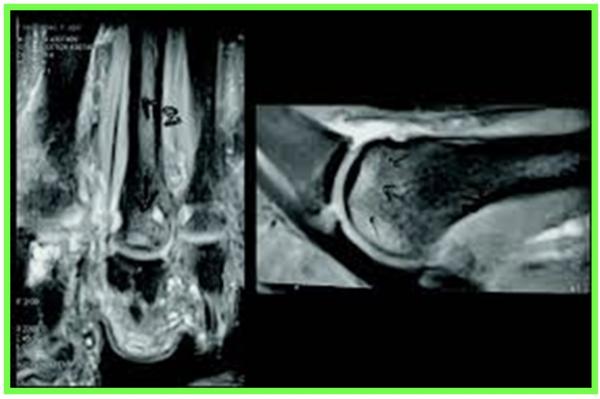

IRM : essentielle pour évaluer la perte de substance et guider la stratégie.

Orientation thérapeutique : < 2 cm : suture + renfort plantaire grêle ; 2–4 cm : suture + Bosworth ; > 4 cm : transfert du long fléchisseur de l’hallux (FHL).

Le transfert FHL est fiable et puissant avec perte de force hallux minime. La voie arthroscopique postérieure élargit les indications et réduit les complications.